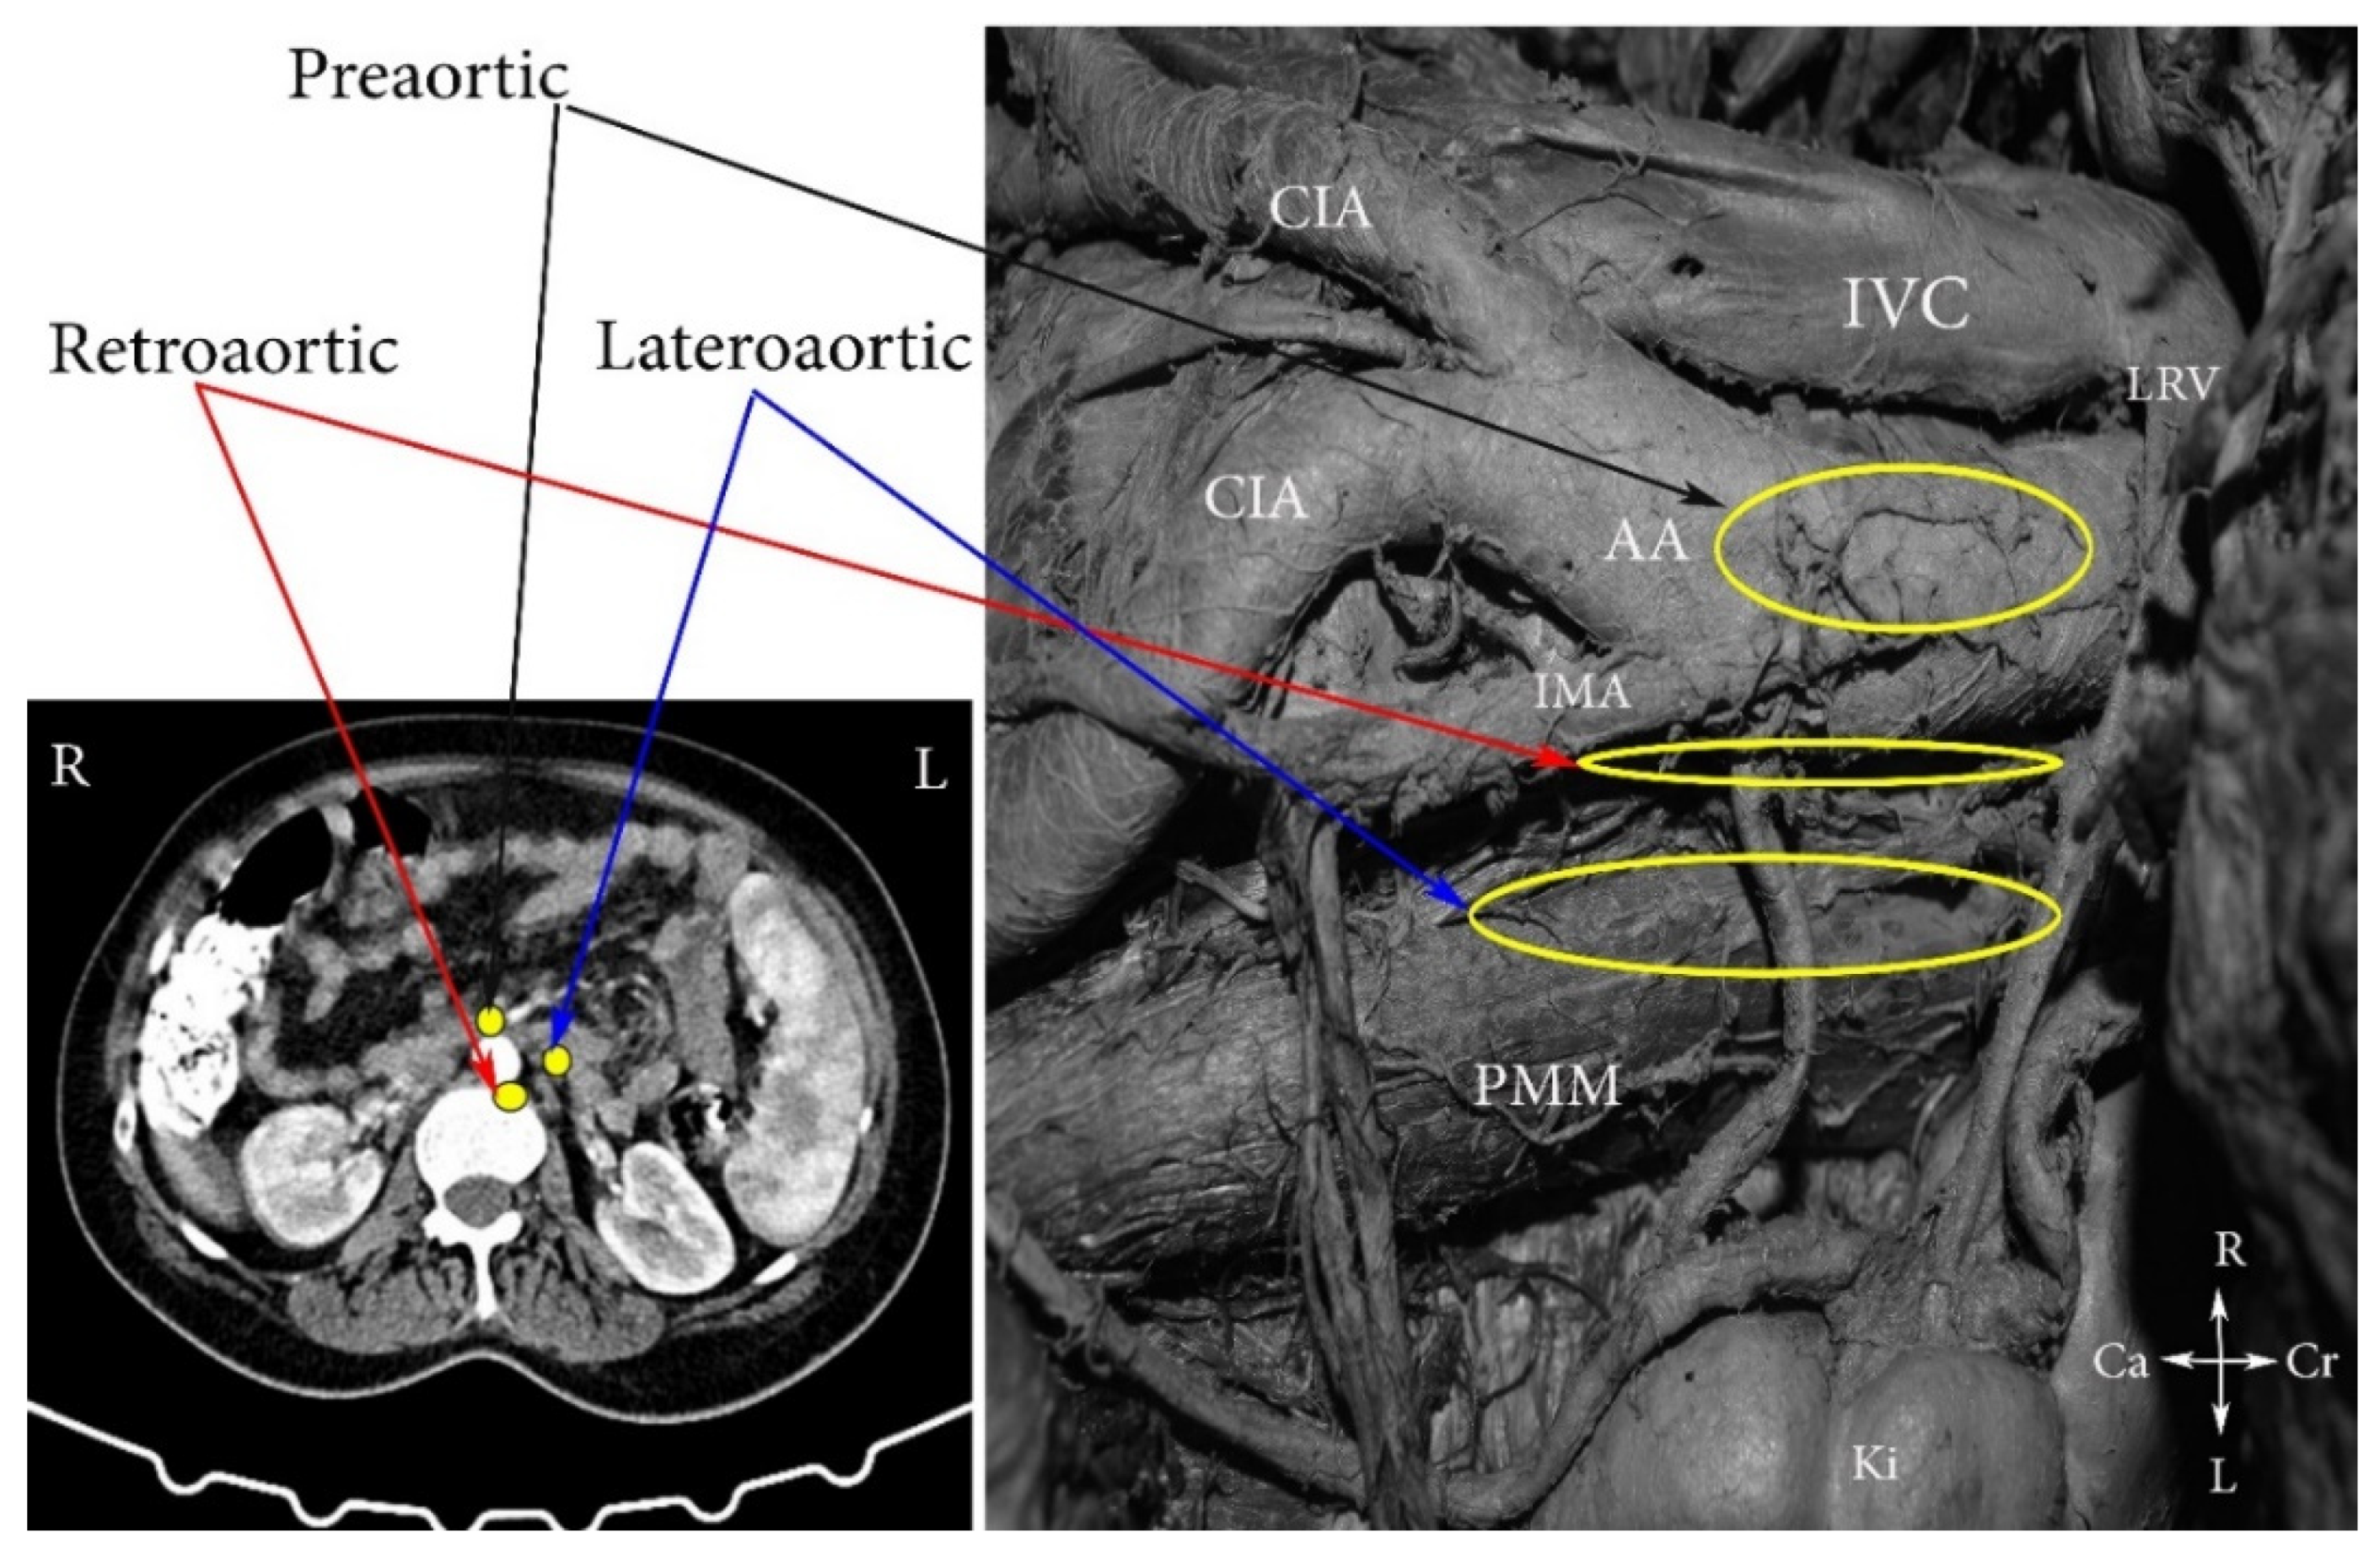

4. Regions and Their Boundaries during PALND

- (A)

- The high paraaortic (supramesenteric) region is limited: ventrally—LRV; medially—AA; laterally—ureter and Gerota fascia; dorsally—IMA; caudally—psoas major muscle.

- (B)

- The low paraaortic (inframesenteric) region is limited: ventrally by the IMA; medially—by the AA, dorsally—the left common iliac artery (CIA); laterally—the ureter and the Gerota fascia, caudally—the psoas major muscle.

- (C)

- The aortocaval or interaortocaval region (includes preaortic and precaval PALNs) is limited: ventrally—LRV, laterally—left—lateral aspect of the AA, right—lateral aspect of inferior vena cave, dorsally—AA bifurcation, caudally—prevertebral fascia, anterior longitudinal ligament and psoas major muscle.

- (D)

- The paracaval region (includes laterocaval and retrocaval PALNs) is limited: ventrally—right renal vein (RRV); dorsally—midpoint of the lateral aspect of right CIA, laterally—right ureter and right psoas major muscle, caudally—the psoas major muscle.